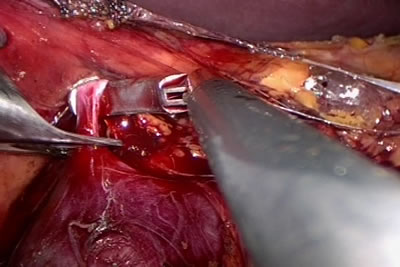

Специальным инструметом взят сосуд.

Накладывается клипса на сосуд.

Наложена клипса на сосуд.